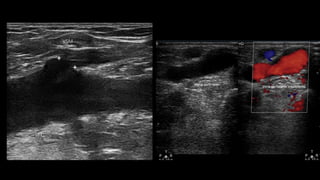

• Safena  Mayor: ØSuperficialmente. ØMínima  presión. ØPlanos  fasciales  adyacentes. ØLocalizada  por  fuera  de  la  fascia  muscular  (unión  músculo-­‐tejido  subcutáneo).

PROTOCOLO  DE  EXPLORACIÓN vLa  exploración comienza en la arcada inguinal, corte transversal a la altura de la  unión safeno-­‐femoral (signo de Mickey Mouse). Se  evalúa el reflujo mediante maniobras de Valsalva con Doppler color y espectral de la VFC, VSM vA nivel de la USF se debe informar si existen afluentes al cayado, su   diámetro, si son o no tortuosas y si son o no insuficientes vMedir el   diámetro de la vena safena magna en el ostium. Ostium safeno entre 6 y 8 mm, el cayado entre 5 y 6 mm, infrapatelar 3 mm.

vSe  evalúa elreflujo en la vena femoral y la vena safena magna en el tercio superior, medio e inferior del muslo. vSi las venas safenas son insuficientes se debe definir  dónde comienza y termina el trayecto insuficiente. vInformar si generan una o   más epifasciales dilatadas (venas varicosas), en   qué   localización y   dónde se encuentra el punto de reentrada al sistema venoso profundo, consignando   también las perforantes. vLa  Safena  menor  mide  entre  1  y  3  mm. vPerforantes  menor  de  3  mm.